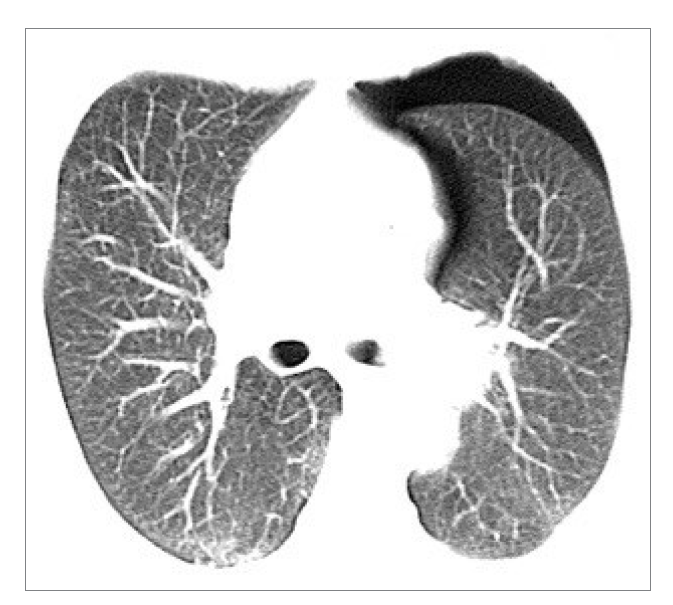

What is this?

Pneumothorax